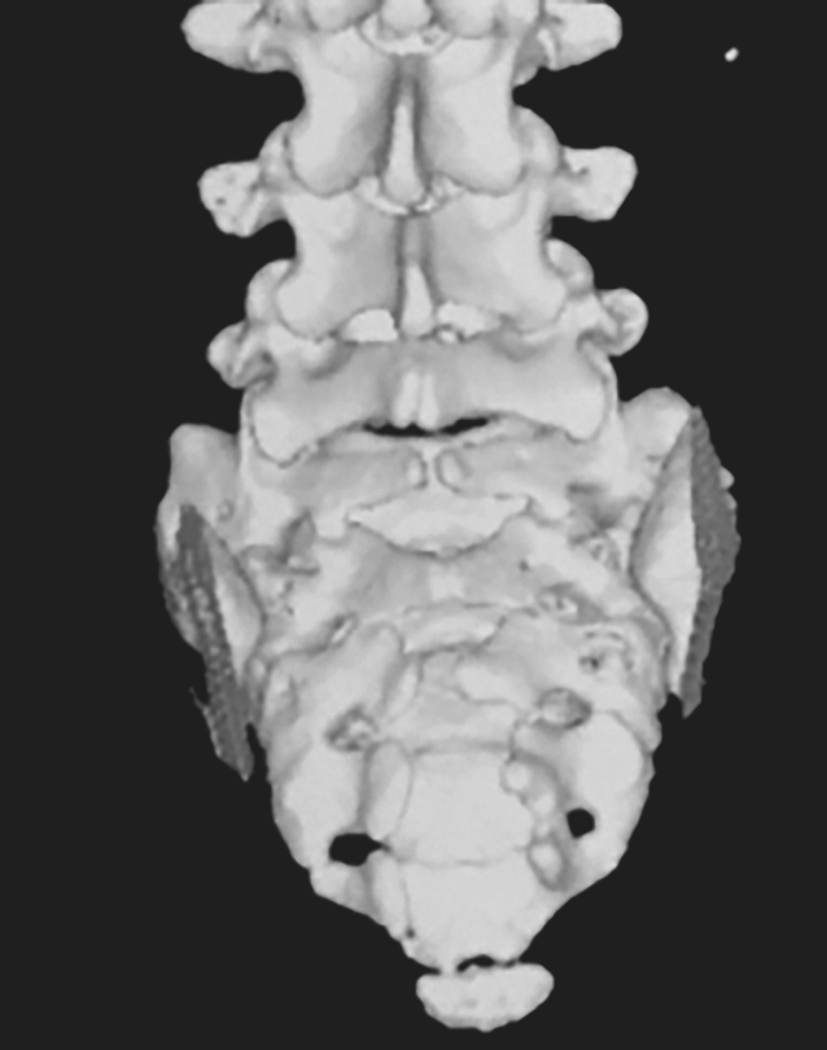

辅助检查:MRI(图4-1-6)示脊柱裂伴脊膜膨出、脊髓栓系低位。CT(图4-1-7)示S 1 、S 3 ~S 5 骶椎裂,伴骶尾部脊膜膨出;脊髓栓系低位可能。

图4-1-6 MRI图像

图4-1-7 CT图像

治疗过程:患儿出生后即发现腰骶部肿物,初时较小,未予特殊处理。目前包块逐渐增大至约10cm×8cm,表面无毛发生长,质软,囊性,按压肿物大小无变化。腰骶CT三维重建示:S 1 、S 3 ~S 5 骶椎裂。腰骶MRI示:①脊柱裂伴脊膜膨出;②脊髓栓系低位。结合病史及症状体征和影像学检查,诊断为:脊柱裂伴脊膜膨出,脊髓栓系。